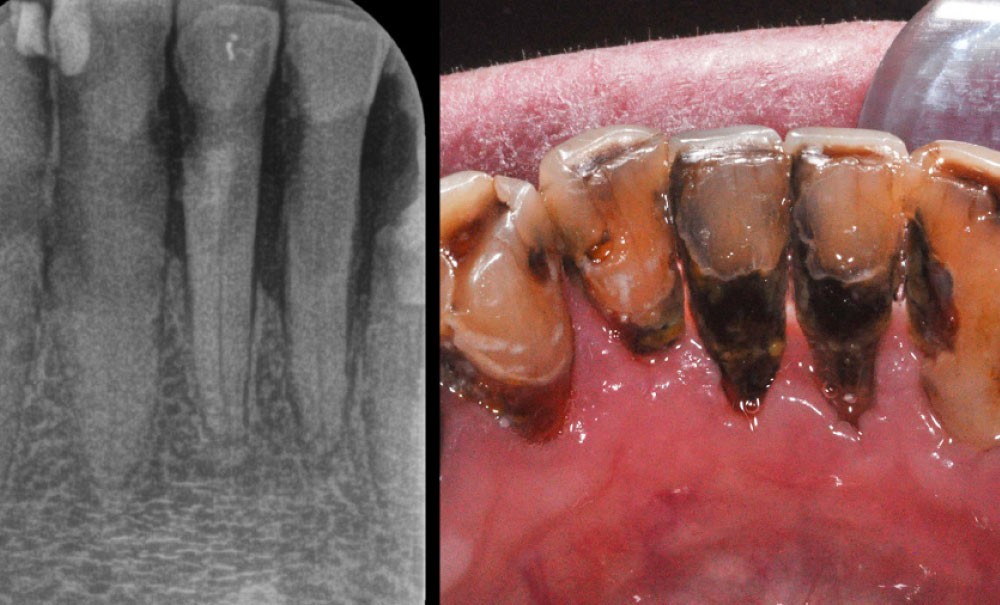

Caries radiculaires chez un patient âgé.

Les caries radiculaires sont parmi les lésions dentaires les plus difficiles à aborder. Le départ de la lésion concerne classiquement une zone radiculaire exposée, située souvent en lingual ou en palatin de la dent affectée, mais la carie évolue ensuite sournoisement en profondeur dans la racine vers des zones difficiles d’accès tant pour l’éviction des tissus atteints que pour la restauration de la cavité par des matériaux insérés en phase plastique. Les patients âgés sont les plus concernés, d’abord parce qu’ils sont davantage prédisposés aux racines exposées suite à la perte du support parodontal, ensuite parce que leur niveau d’hygiène est moins efficace alors que la configuration des zones à nettoyer est plus complexe, enfin parce que des conditions générales ou locales (xérostomie, pathologies générales, prises médicamenteuses…) favorisent le développement de ces lésions. Ces dernières évoluent rapidement, jusqu’à compromettre la survie des dents concernées.